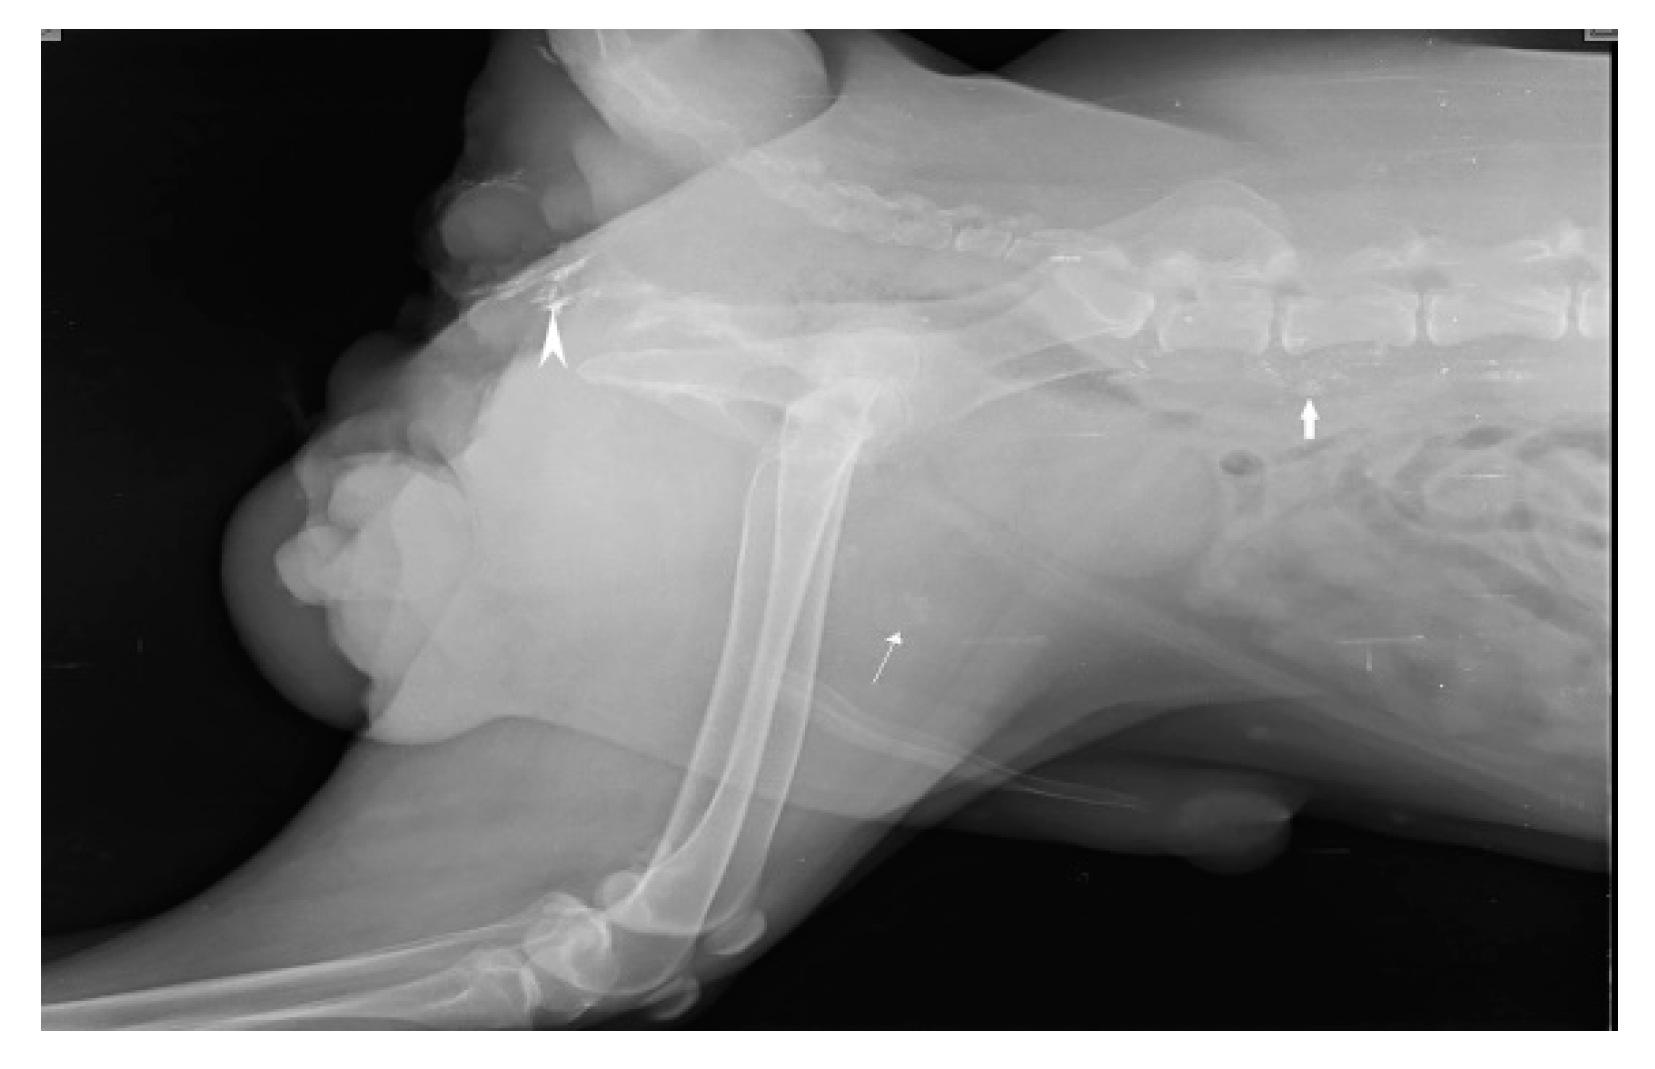

SLN mapping for 20 primary tumors (MCT-11, SCC-3, basal cell carcinoma-1, canine papillomatosis-3, cutaneous plasmocytoma-1, sebaceous gland adenocarcinoma-1) of skin and subcutaneous tissue is performed with four IL methods. MCT weighing 7.8 kg, 3kg, 1.9kg, 1.8kg, 300g, 250g, and lymph nodes weighing 3g, 5g, 10g, up to 90g are excised through en bloc surgical resection with a broad margin. According to the Patnaik grading system (Patnaik et al., 1984), the clinical staging of 11 MCT is Grade III (n=5), Grade II (n=3), and Grade I (n=3). In MCT(n=11), IL with Lipiodol results in 100% detection rate. SLN are detected within 24hr of injections along with gentle messaging in Lipiodol whereas 2 min of injection in iohexol(n=2). Six of the 15 SLN, discovered through cytology and biopsy are determined to be non-metastatic, whereas the other 9 are found to be positive for metastasis. IL was unable to detect any lymph node in rest 5 cases. The SLN for tumors in the front leg is the cervical lymph node as shown in Fig.3.

Figure 3. Cervical lymph node (arrow head) as sentinel lymph node for mast cell tumor (solid star) of front leg.

Preprints 77141 g003